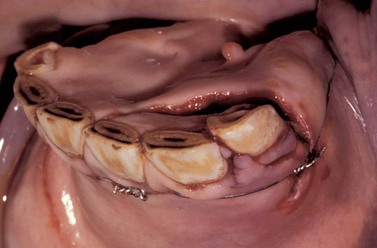

Injuries to the hard palate are rare but may accompany severe head trauma (Fig. 9.13). In some circumstances, there may be an underlying fracture of the palatine processes of the premaxillary and/or the maxillary bones. In general, these injuries can be left as open wounds, to heal by second intention. However, if the hard palate injury has caused an oronasal fistula, such lesions should always be repaired surgically. A suspected oronasal fistula may be confirmed by a combination of thorough clinical and endoscopic examinations, and by radiography after oral administration of barium sulfate. While such a fistula may heal by second intention, surgical repair should be attempted if the site is accessible. It may be possible to repair the defect by debriding the wound and curetting any area of oronasal mucosal continuity and simply suturing the palatal mucosa with interrupted, polydioxanone sutures (Fig. 9.14). If the injury cannot be repaired adequately in this manner, it may be possible to close the defect by creating a mucoperiosteal flap, or by making tension-relieving incisions in adjacent portions of the palate and then suturing the defect. Care should be taken to avoid damaging the palatine blood supply. Post-repair feeding should be carried out by nasogastric intubation for the first 4 or 5 days to reduce the risk of suture dehiscence. If the rostral portion of the skull is grossly unstable following a maxillary or premaxillary injury, the fractures may require surgical repair. However, it is surprising how frequently horses with such major injuries respond successfully to conservative management.

image

Fig. 9.13 This horse sustained severe trauma to the maxilla which resulted in a fracture of the premaxillary bone and laceration of the hard palate. There was direct continuity between the oral and nasal cavities.

Fig. 9.14 This is the surgical repair of the injury illustrated in Fig. 9.13. The fracture has been reduced with cerclage wire after radical debridement of the site. The palate has been sutured partially using simple interrupted and vertical mattress sutures of 4 metric polydioxanone. The horse made an uneventful recovery, and the cerclage wire was subsequently removed.